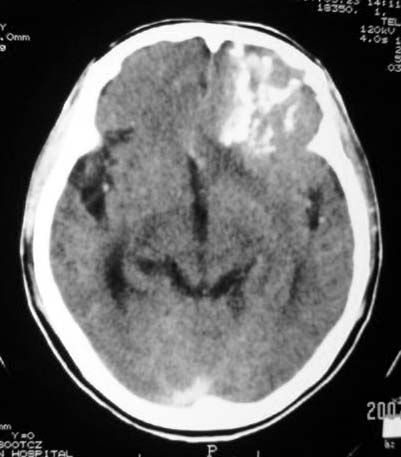

标题: CT7268:左额顶部病变增强片. [打印本页]

标题: CT7268:左额顶部病变增强片.

比较典型的少枝胶质细胞瘤ct表现,局部额骨垂直板有侵蚀变薄。

左额叶病灶内条片状高密度是钙化吗?是的话考虑少支胶质瘤可能大。不然有脑血畸形伴出血可能。

左侧额顶叶有条带状钙化的不规则形占位,增强呈不均匀轻度强化,局部颅骨受侵蚀变薄,典型的少支胶质细胞瘤。

比较典型的少枝胶质细胞瘤ct表现,局部额骨垂直板有侵蚀变薄